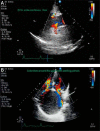

Coronary artery fistulas are rare coronary-cardiac anomalies, which occasionally become symptomatic. We herein report a case of a 54-year-old woman with a huge conus branch aneurysm resulting from an abnormal fistula between the conus branch and the upper portion of the right atrium, which was successfully removed by surgery.